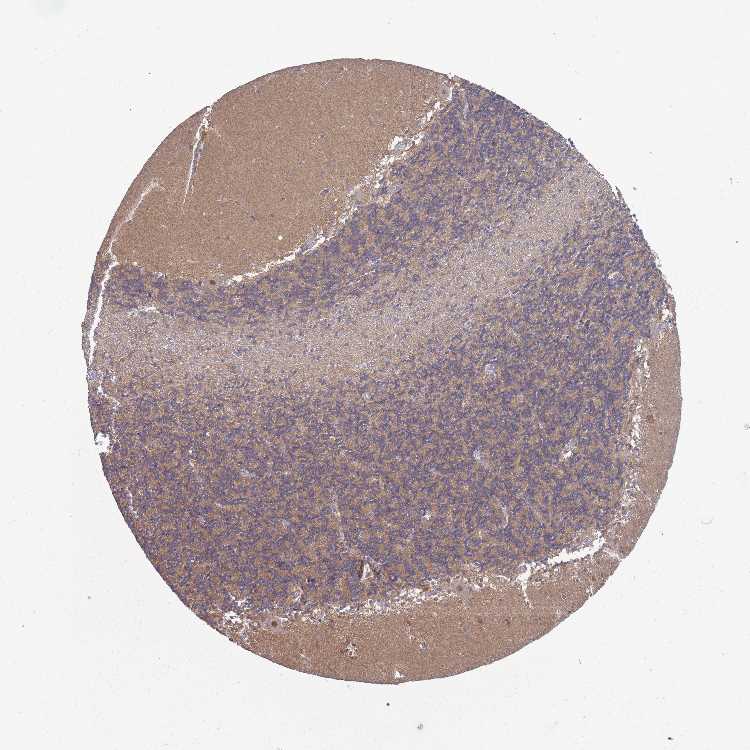

CEREBELLUM - Antibody stainingi

Antibody staining in the annotated cell types in the current human tissue is reported as not detected, low, medium, or high, based on conventional immunohistochemistry profiling in selected tissues. This score is based on the combination of the staining intensity and fraction of stained cells.

Each image is clickable and will lead to virtual microscopy that enables deeper exploration of all samples and also displays staining intensity scores, fraction scores and subcellular localization as well as patient and tissue information for each sample.

Antibody HPA021139

Purkinje cells High

Cells in granular layer Low

Cells in molecular layer Not detected